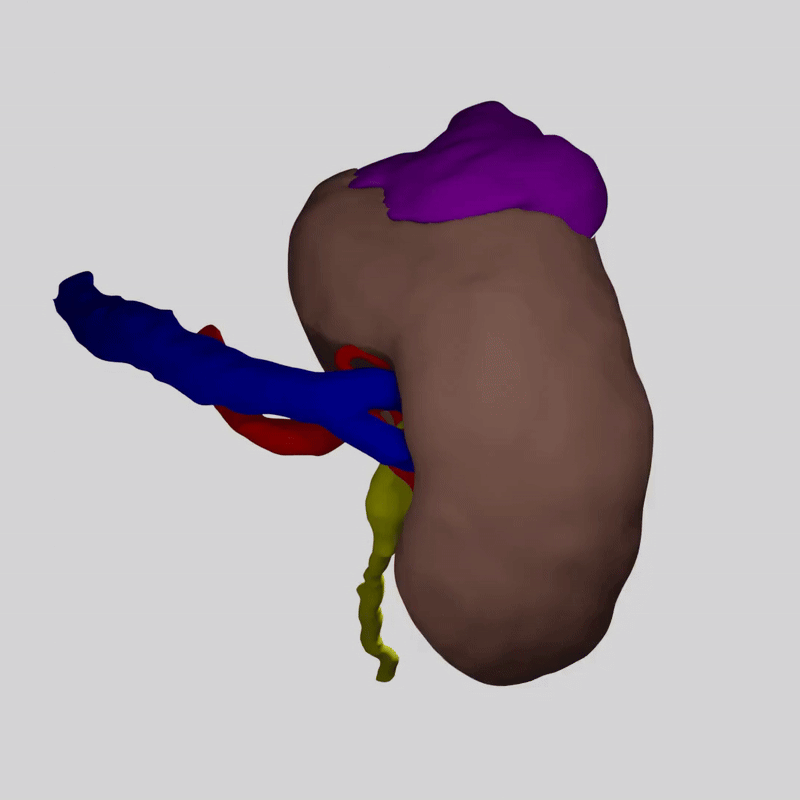

AssistoAR™ създава персонализиран 3D модел на бъбрека и неговата анатомия за всеки пациент.

Известната компютърна томография до триизмерна реконструкция на вашата анатомия.

Моделът показва:

🔹 Точното управление на тумора

🔹 Разклоненията на артериите, които кръвоснабдяват бъбрека

🔹 Каква част от бъбрека може да бъде запазена безопасно

AssistoAR™ създава и специална карта – NaVa (Navigation of Vascularity).

Представете си бъбрека като разделен на цветни зони.

Всяка зона получава кръв от различен клон на бъбречната артерия.

Когато хирургът види тази карта, той може да прецени:

🔹 Кои части на бъбрека се хранят от кои съдове

🔹 Колко от органа може да се запази при операцията

🔹 Как най-безопасно да загубите тумора